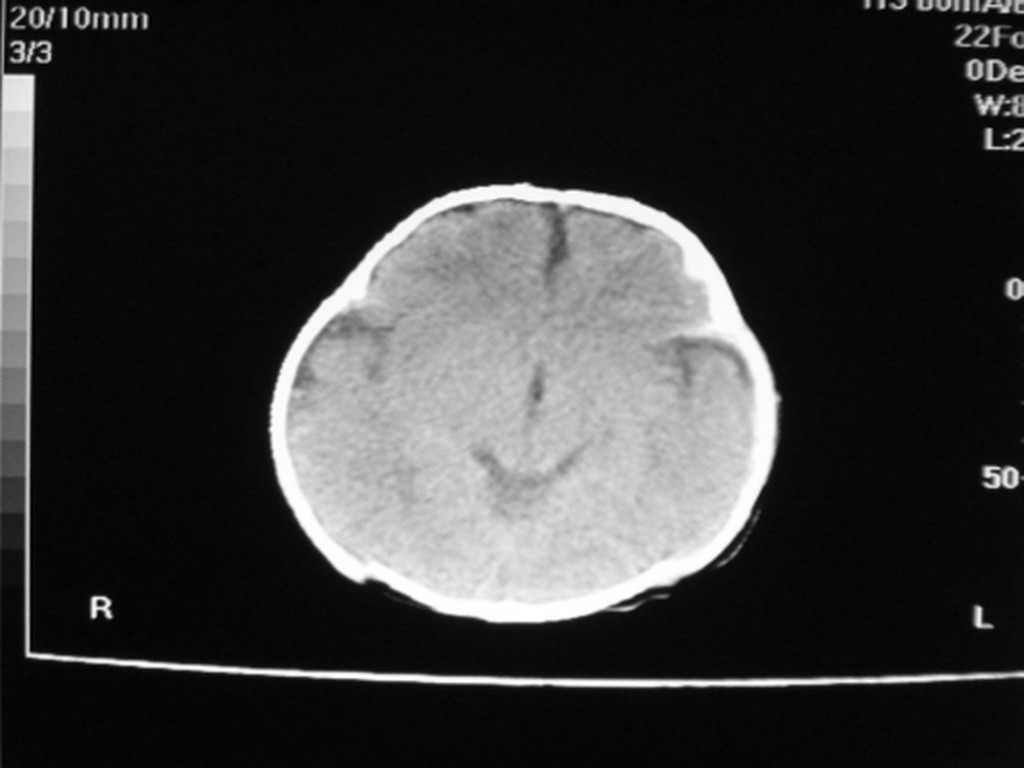

标题: PED1877:女,20余天,突发抽搐,双眼凝视。 [打印本页]

女,20余天,突发抽搐,双眼凝视。